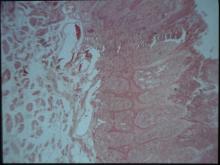

仔羊消瘦,除此之外主要肉眼可見明顯病變集中於唇及舌部(圖1)。可見多發性增生

性腫塊病變伴隨膿瘍灶,並形成痂皮。其他內臟無明顯肉眼病變。三、 組織病變: 口唇部皮膚可見表皮棘細胞層增生(圖2)、水腫變性、氣球樣變性;部份表皮細胞角

化過度;表皮層與真皮層之間有紅血球浸潤;表皮層有炎症反應及多數炎症細胞浸潤;

細胞質內可見疑似嗜酸性質內包涵體(圖3)。四、 實驗室檢驗: 1.